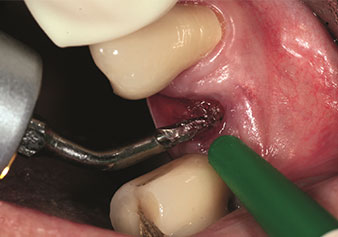

Alveolar management

One application, which is often underestimated is the atraumatic extraction of tooth roots or root fragments in the scope of alveolar management. The fine periotomes, which are currently available in two versions (EX1 and EX2 from W&H), can also be used to remove teeth which have previously undergone special endodontic treatment or ankylosed roots with ease. This results in extraction alveoli where both the hard and soft tissue are fully intact as it is generally possible to avoid reflection.

This establishes the optimal basis for subsequent or immediate implant treatment (Figures 1 and 2 included with the kind permission of Dr Torsten Conrad, Bingen a. Rhein).